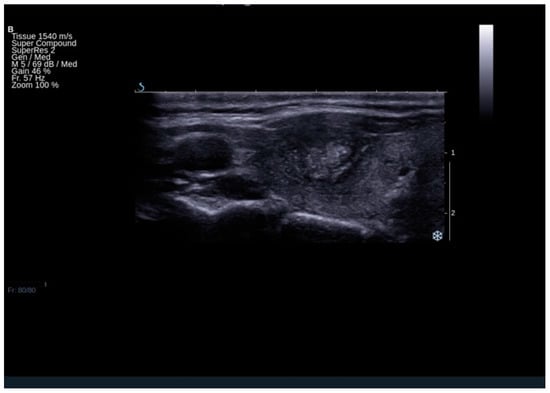

Patients finally diagnosed with FTC were more than 10 times more likely to have a tumor protrusion (Figure 3)—OR (95% CI): 10.19 (2.62–39.71) (Tables S2 and S13a,b). The analysis included 633 patients and the group proved to be homogenous (test for heterogeneity: I2 = 0.0%, p = 0.4350. The specificity (95% CI) of this feature reached 1.00 (0.99–1.00) with low sensitivity (95% CI) of 0.06 (0.03–0.09).

Figure 3.

The result of ultrasound examination demonstrating thyroid lesion, which turned out to be follicular cancer on histopathological examination. The lesion presents tumor protrusion, irregular margins, microcalcifications, and heterogeneous echostructure.

Our meta-analysis demonstrated that the sonographic feature the most strongly increasing the risk of FTC, but not underlined in the previous studies, was capsule protrusion. Although only two studies took into account this feature, it turned out to be the substantial differentiating factor between FTA and FTC, with an OR at the level of 10.19 [13,32]. Capsule protrusion towards the surrounding structures with or without visible capsule disruption can be considered as a risk factor for the extrathyroidal extension, which is equal to 61% in these subjects, while 31% for macroscopic invasion [40].